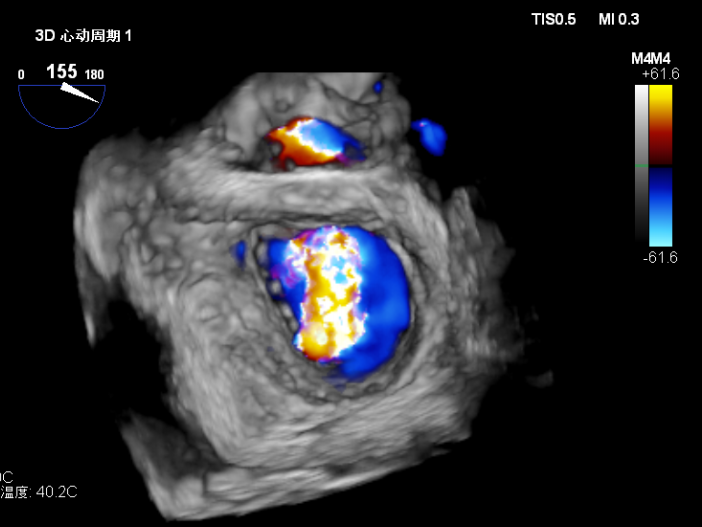

2.X-plane切面调整瓣膜夹的位置:主要定位PISIA最明显的A2/P2区,分别二尖瓣交界联合切面和 LVOT切面调整夹子轴向,同时在3D切面上观察夹子方位和区域,瓣膜夹位置良好,轴向和方位均理想后,捕获A2/P2偏1区处的前后瓣叶,逐渐关闭瓣膜夹,TEE显示二尖瓣反流明显减轻至微量,3D视角显示组织桥连续完整,瓣叶抓捕稳定。彩色血流提示微量的瓣膜反流,测量平均跨瓣压差3mmHg,复查左上肺静脉血流频谱恢复正向,手术效果理想,逐步释放瓣膜夹系统撤出体外。